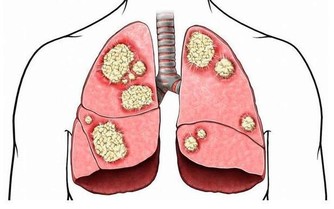

然而,在某些情況下,高血壓可能會顯示出一些症狀,這可能表明你需要去看醫生了。這九個需要注意的標誌,包括頭痛、呼吸短促、頭暈、胸痛、心悸、鼻出血、胃痛、發燒和視力模糊。其中一些症狀,比如頭痛和頭暈等,跟高血壓有較為明顯的關係,雖然你經常忘記把它們聯想在一起。

但還有一些跡像看起來似乎很難跟高血壓聯繫起來,但它們確實有關係。

比如,眼部問題和噁心,可能是血壓過高或大腦壓力增加的特殊跡象。